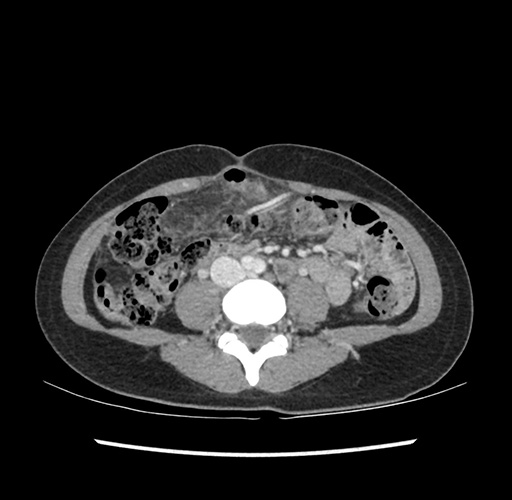

Imaging Analysis

Look through the patient's CT scan to identify any areas of concern for the necessary procedure.

Based on your CT findings, which issue(s) would give reason for "planned slowing down moment(s)" in this case?

Considering a standard left lateral sectionectomy procedure, what step(s) of the operation would you do differently in this case ?